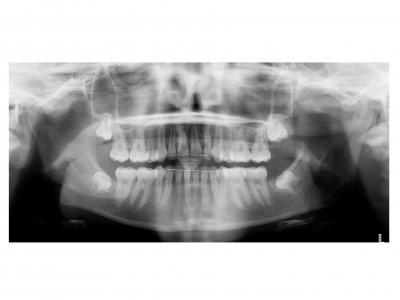

Voici les deux patientes traitées

Ici, dans les deux cas, les deuxièmes prémolaires ont été extraites et les traitements ont duré 18 mois.

Dans le deuxième cas, le désencombrement a fermé les espaces en 6 mois. Les incisives ont été surtorquée pour avoir un meilleur soutien labial. Le traitement qui avait bien débuté, a été difficile à finir, car les anatomies coronaires et radiculaires étaient perturbées.

Si on n'avait pas extrait dans le premier cas, cela imposait une ouverture de l'espace de la 24 et donc une avancée des incisives supérieures et donc une aggravation de la béance. Dans le deuxième, on sortait les racines de l'os alvéolaires (racines déjà apparentes au départ). Même une expansion associée à du stripping et une distalisation des secteurs latéraux n’auraient pas permis de préserver ce parodonte fin.